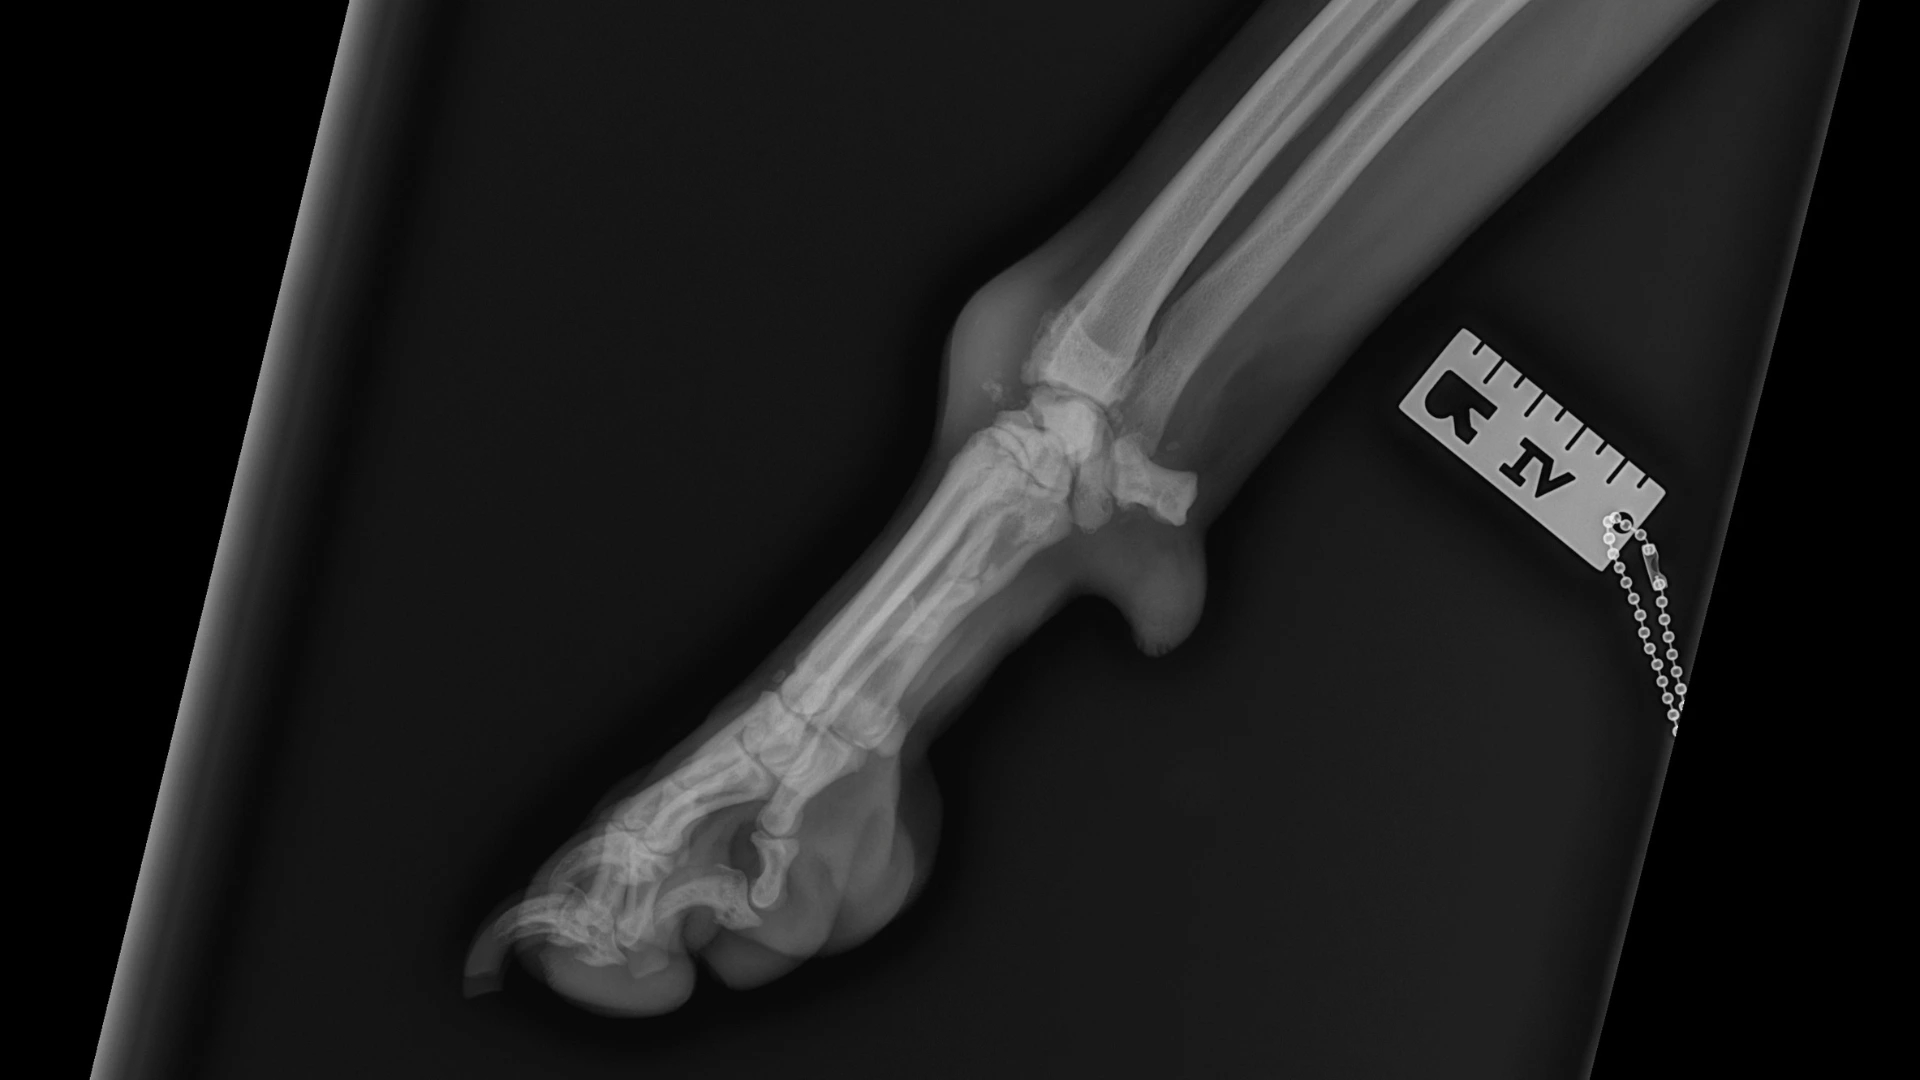

After referral by Max’s primary vet, clinical examination and imaging revealed the underlying issue: a fracture of the radiocarpal bone, coupled with severe osteoarthritis. Scans also showed swollen tissue with some calcium buildup sitting on top of Max’s carpal joint.

The diagnosis was clear: a procedure to fuse Max’s wrist joint (right-sided pancarpal arthrodesis) would be necessary to restore function, maintain Max’s mobility and eliminate pain.

One of Max's small wrist bones (the radiocarpal bone) had broken into pieces, with a fragment pushed out of position. This broken bone, combined with the severe arthritis, meant the joint could no longer function normally.